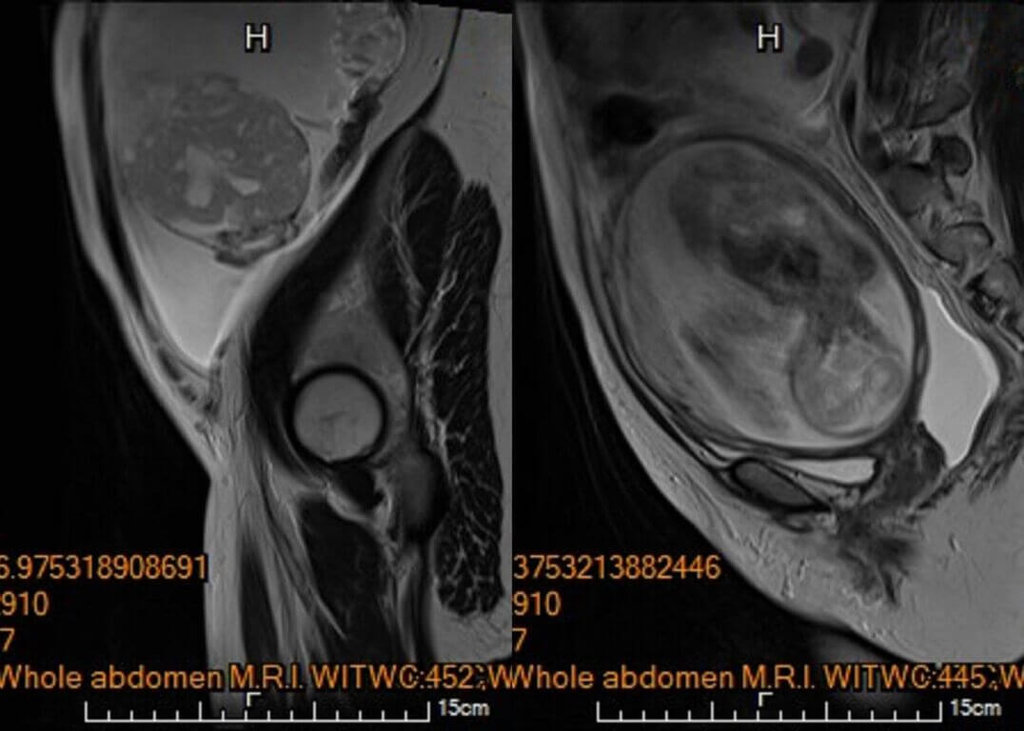

李小姐告訴醫師確實有明顯的進食與呼吸困難疑似腸胃道問題,為求謹慎,針對腹水檢體進行細胞檢驗,雖未能於腹水內發現癌細胞,腹部核磁共振影像顯示腫瘤疑似來自左側卵巢,且惡性風險極高,高度懷疑是懷孕中合併卵巢癌。懷孕中發現惡性腫瘤,讓她萬念俱灰。

考量李小姐胎兒屬於極低體重兒,預估體重尚不滿500公克,早產存活率太低,加上惡性腫瘤妊娠中手術的風險太高,陳楨瑞評估風險後決定,儘速安排手術切除腫瘤,不論腹腔內轉瘤蔓延嚴重度,均保留子宮與可能未被侵犯的右側卵巢輸卵管,以最大努力讓腹中胎兒能長大到足月。

陳楨瑞說,幸運的是,李小姐進行手術時腹腔內並沒有發現腫瘤擴散或轉移跡象,子宮與右側卵巢輸卵順利被保留住了,子宮內胎兒也未受到手術影響。雖然病理報告雖證實為卵巢癌,但是歸屬於低度惡性「幼年型顆粒細胞瘤」,免於後續在懷孕期間接受化學治療。